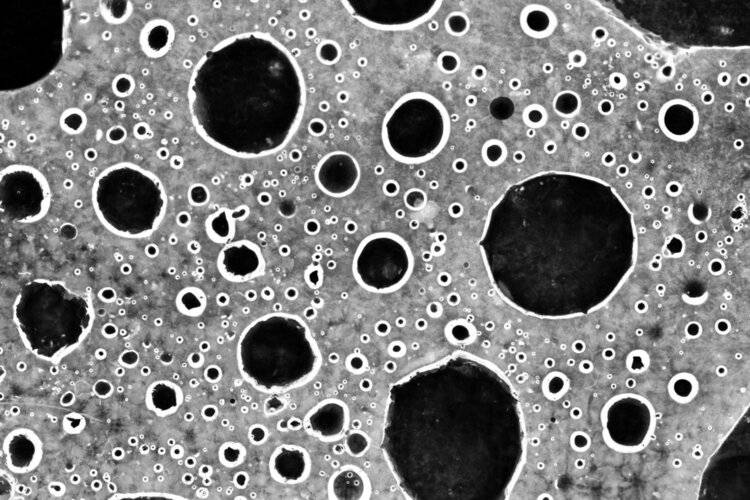

文章图片